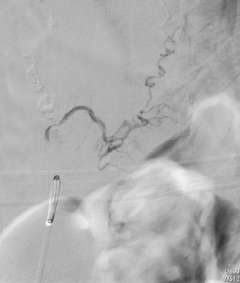

Depending on the lesion, the best treatment plan changes. For intramedullary AVMs, partial or palliative treatment is sometimes an option since complete obliteration may carry a much higher chance of causing neurological deficits than conservative management or partial treatment (Figure 3).

Figure 3: A palliative / partial Catheter Treatment for a Spinal AVM.

Multiple arteries feeding the spinal AVM. There are aneurysms in the feeding arteries.

Two feeding arteries harboring the aneurysms were obliterated using catheter embolization techniques.

The aneurysms were completely obliterated, and the risk of bleeding was reduced. However the AVM receives blood flow from the other feeding arteries.